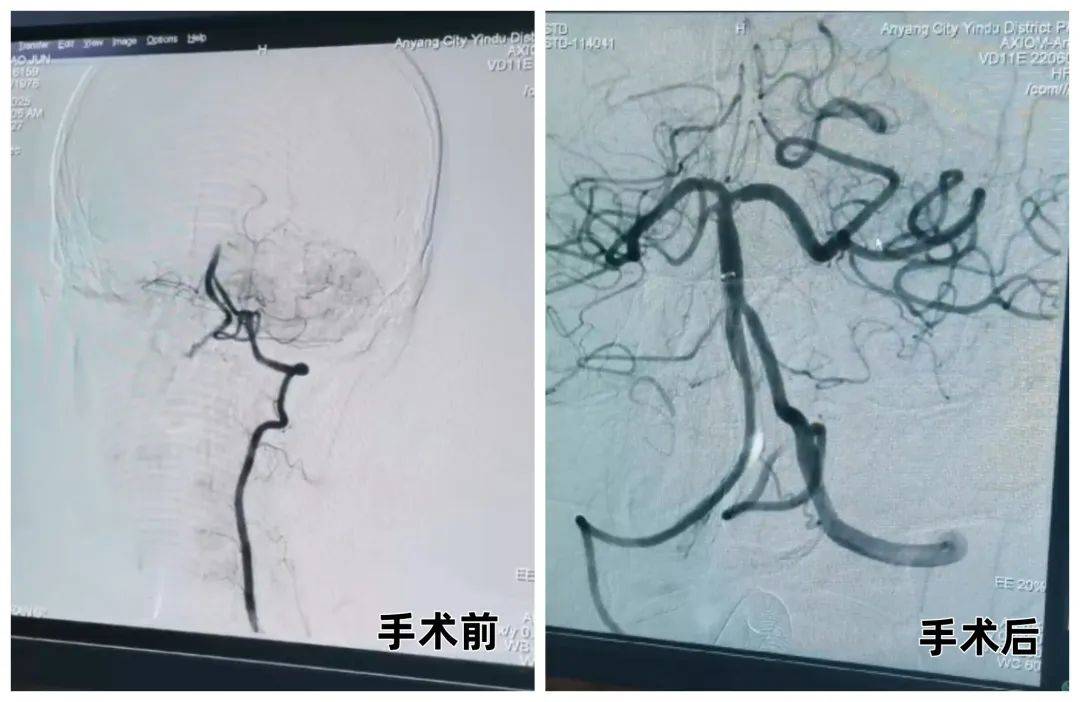

04椎動脈閉塞支架植入術(shù),49歲患者24小時(shí)內(nèi)重獲行動能力

49歲的何大哥因“頭暈1小時(shí)50分鐘伴言語不利”入院,頭顱核磁及 DSA 檢查顯示基底動脈及右側(cè)椎動脈閉塞。治療團(tuán)隊(duì)先予替奈普酶溶栓,隨后緊急實(shí)施基底動脈取栓 + 右側(cè)椎動脈起始段球囊擴(kuò)張支架置入術(shù)。術(shù)后第二天,患者頭暈及言語不利癥狀明顯減輕,已可自行活動。